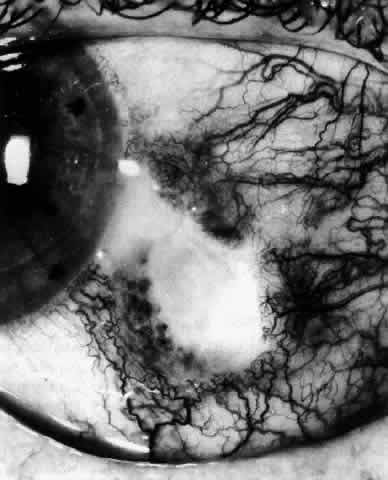

Fig. 30. Diffuse anterior scleritis. During the acute attack, the vessels are dilated

and distorted. New vessels or large vessels not normally seen have

appeared adjacent to the limbus. Fig. 30. Diffuse anterior scleritis. During the acute attack, the vessels are dilated

and distorted. New vessels or large vessels not normally seen have

appeared adjacent to the limbus.

|